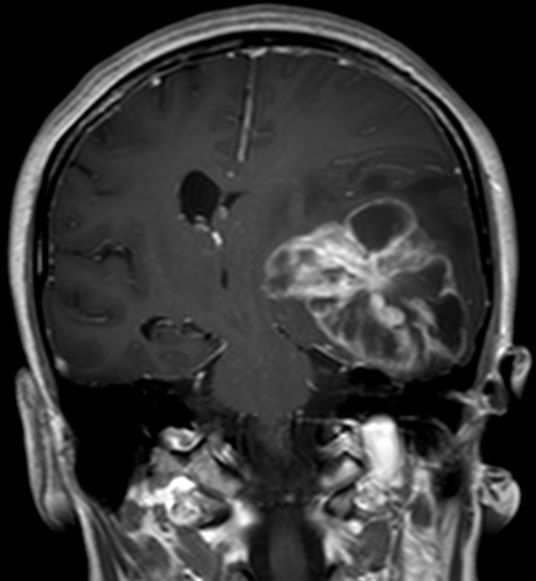

Schmetterlingsgliom des hinteren Balkens |

62-jähriger Mann mit torkeligem Gang, Amnesie und Verwirrtheit. Schmetterlingsgliom des hinteren Balkens.![]() |

![]() |

![]() | |